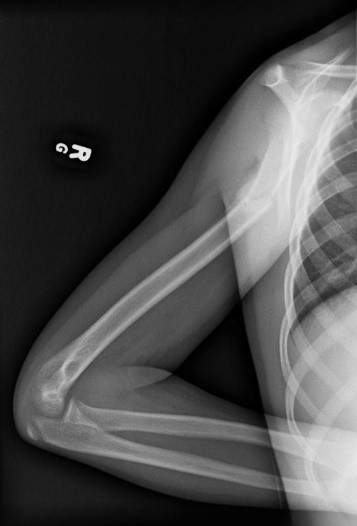

Ангіографія